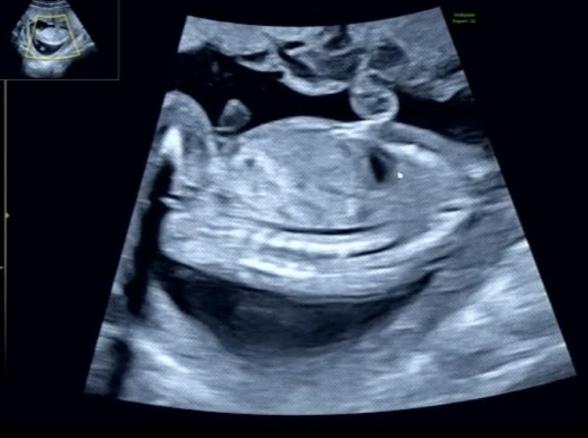

13wに胎児ドックを行った時には男の子かもと言われていましたが

17wでの検診の時には女の子だと言われました!

次の検診まで確定ではないとは言われていますが、、

拝見していて、はっきりと男の子のシンボルはわからず、女の子のサインとされるお股のあたりに見られるようになる葉っぱのマーク、サインが、添付をしてくださったものからは分かりませんでした。

せっかくたくさん載せてくださったのに、大変申し訳ありません。

また次回の健診でも先生にご確認いただけたらと思います。